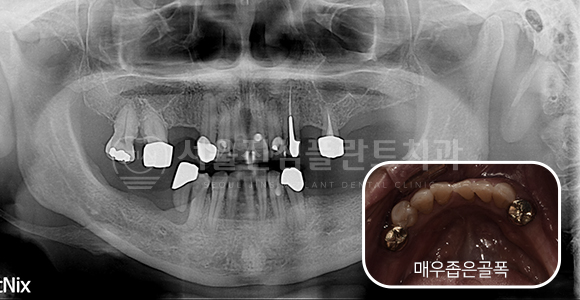

상악동 거상 측방접근 + 고난이도 뼈이식 임플란트

-

BEFORE

AFTER

상악동 거상 측방접근 + 상악 전치부 고난이도 뼈이식